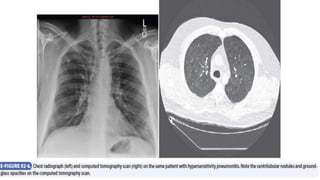

• Findings on chest radiography are diverse, with focal patchy

consolidation or a diffuse ground-glass appearance in acute

hypersensitivity pneumonitis micronodular and reticular shadowing in

subacute forms; and diffuse, predominantly upper lung zone

reticulation with honeycombing in the chronic form. Chest radiograph

results may be normal in up to 30% of patients with significant

physiologic abnormalities.

• On HRCT, small centrilobular ill-defined nodules of ground-glass

densities are seen, along with evidence of mosaic attenuation

(trapped air) as a result of concomitant bronchiolitis and upper lobe